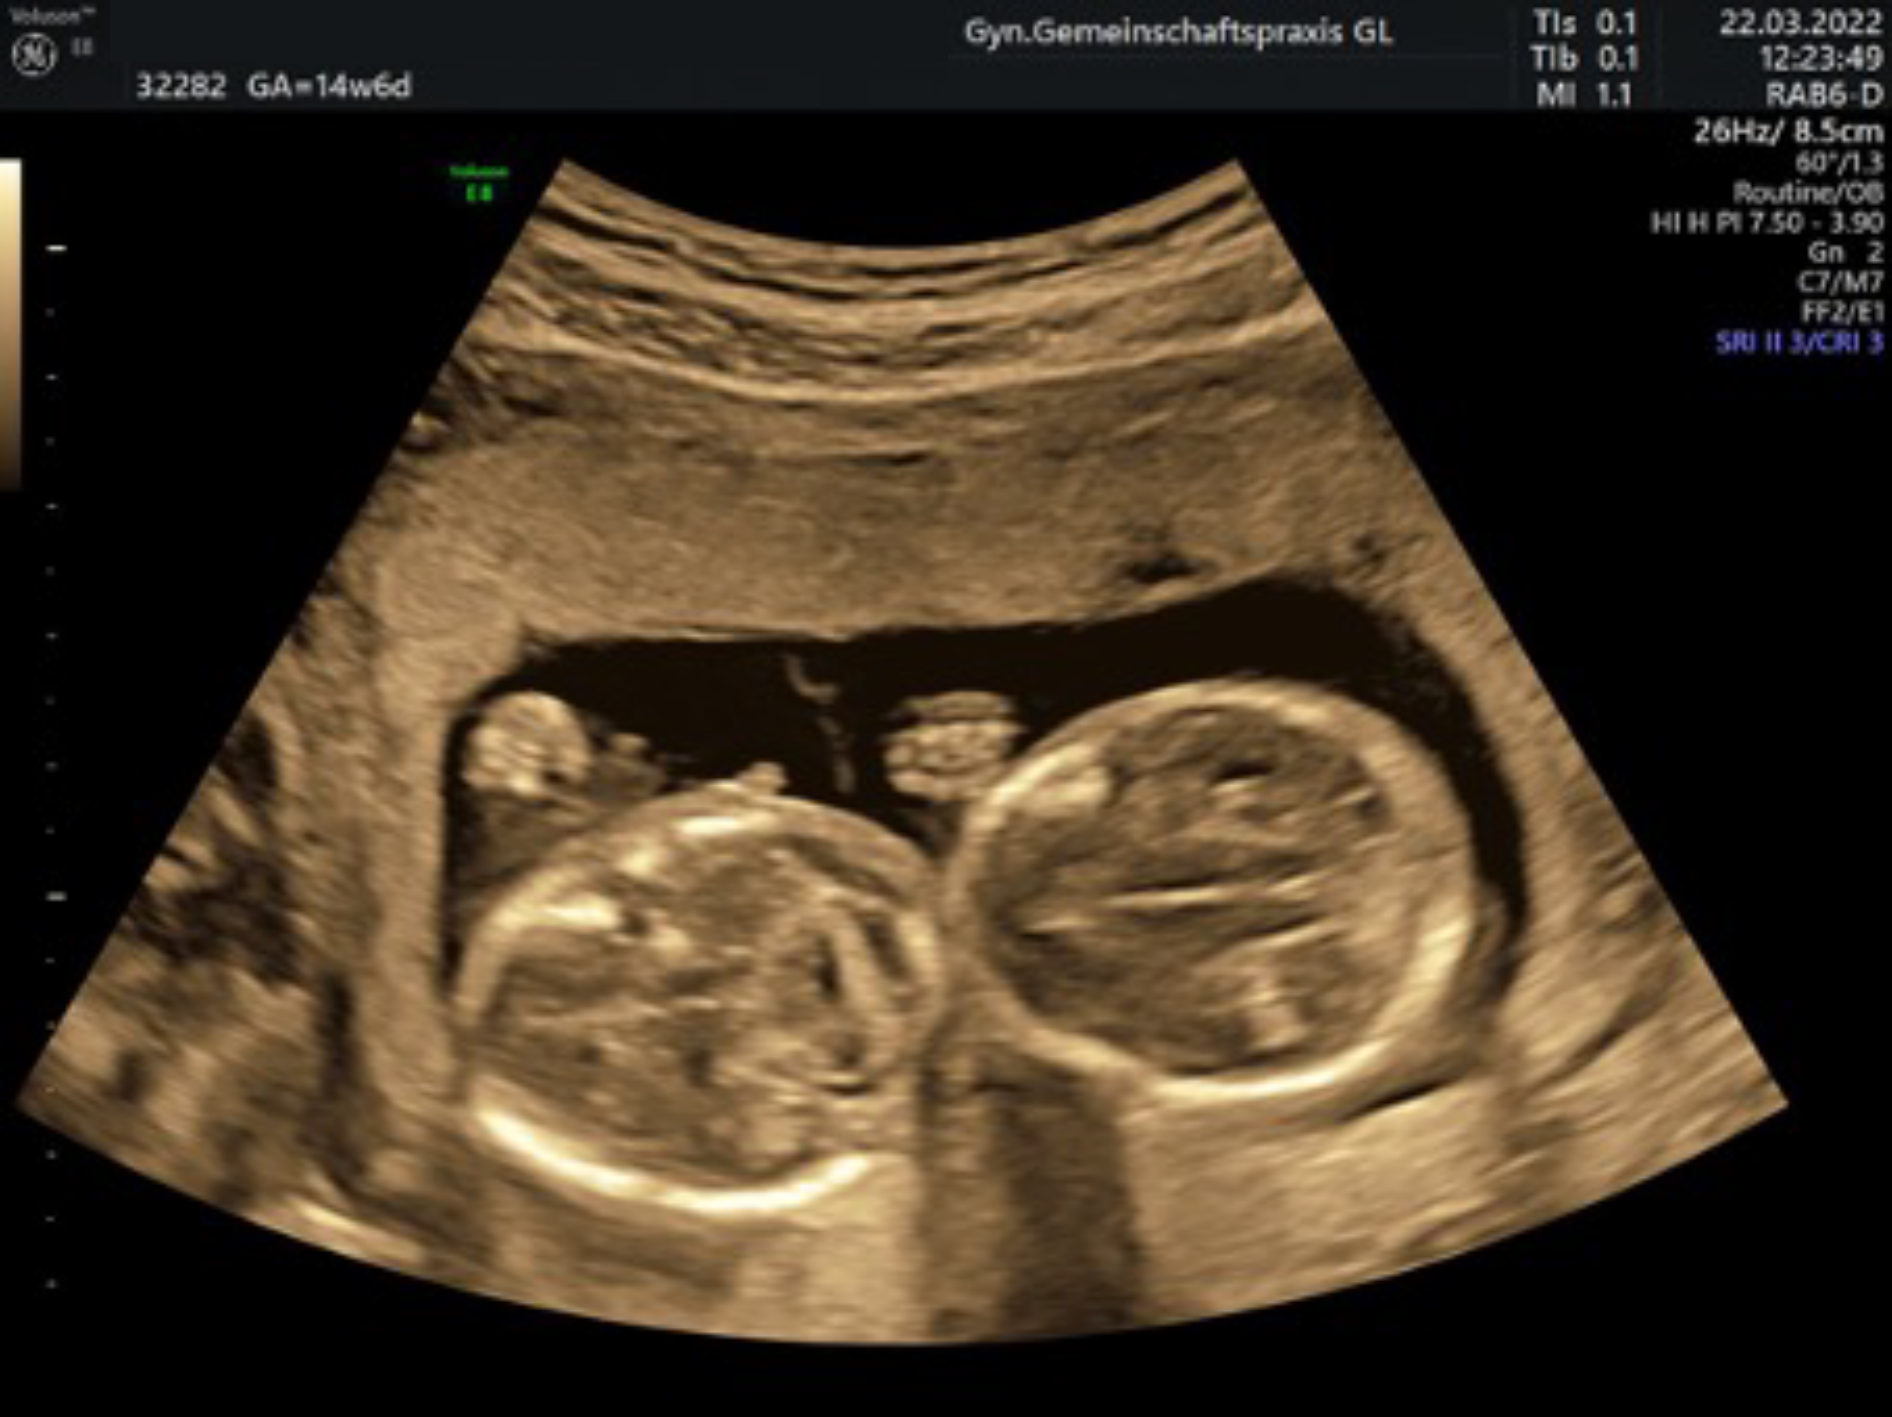

Bei Mehrlingsschwangerschaften wird die invasive Diagnostik für jedes Kind einzeln durchgeführt.

Für Mehrlingsschwangerschaften ist der NIPT z Zt nicht sinnvoll nutzbar.

Bei besonderen Indikationen (ab 35 J, Mehrlinge, best. Vorerkrankungen, kranken Kindern in der Vorgeschichte oder der Familie, schlechten Sichtbedingungen oder kindl. Auffälligkeiten) wird die sog. Organdiagnostik durchgeführt.

Ultraschall in der 20. – 22. Schwangerschaftswoche mit Organfehlbildungsdiagnostik und Untersuchung der Blutversorgung nach den Richtlinien der DEGUM Stufe II

Mit einem hochauflösenden Ultraschallgerät werden dabei alle Organsysteme des Kindes gründlich untersucht um nach Hinweisen auf Fehlentwicklungen zu suchen. Besonderes Augenmerk liegt dabei auf dem Herzen, dessen richtiger Aufbau und Funktion mithilfe farbcodierter Blutflussmessungen (Doppleruntersuchung) überprüft wird.